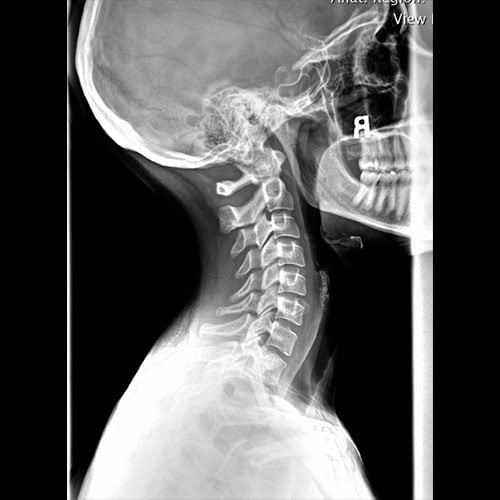

Normal Lat Cervical